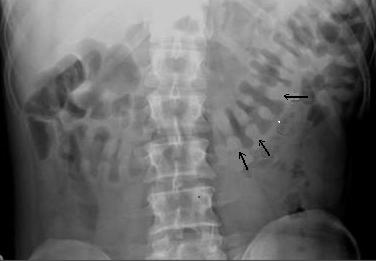

Image de aerique du colon et

image en empreinte de pouce ( fleche noire ) . du

colon transverse et colon descendant |

Complication de pneumatosis du

colon parfois se presente : Image de couche de air

intra -parietale du colon ( fleche blanche ) . |